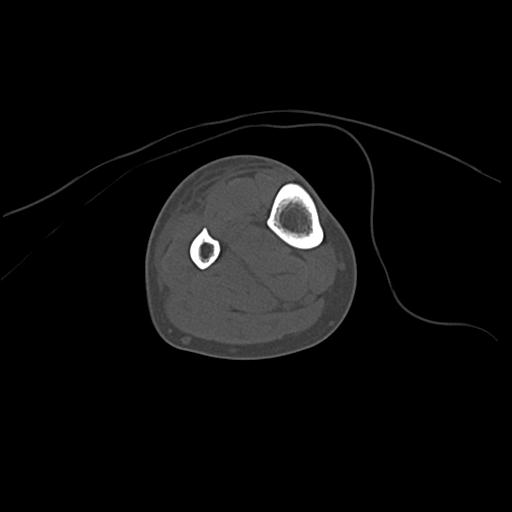

49554 3/13 膝 4R 3/16 4R 1/18 2R 78歳男性 膝蓋骨骨折